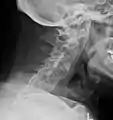

X-rays

The earliest changes demonstrable by plain X-ray shows erosions and sclerosis in sacroiliac joints. Progression of the erosions leads to widening of the joint space and bony sclerosis. X-ray spine can reveal squaring of vertebrae with bony spur formation called syndesmophyte. This causes the bamboo spine appearance. A drawback of X-ray diagnosis is the signs and symptoms of AS have usually been established as long as 7–10 years prior to X-ray-evident changes occurring on a plain film X-ray, which means a delay of as long as 10 years before adequate therapies can be introduced.[24]

Options for earlier diagnosis are tomography and MRI of the sacroiliac joints, but the reliability of these tests is still unclear.

Lateral X-ray of the mid back in ankylosing spondylitis

Lateral X-ray of the neck in ankylosing spondylitis